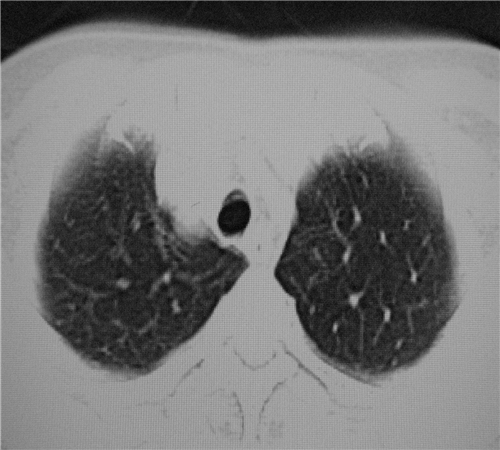

标题: CT26849:女67岁反复胸痛两天余,临床考虑夹层。 [打印本页]

标题: CT26849:女67岁反复胸痛两天余,临床考虑夹层。

双下肺感染,右侧显著。有无夹层,增强扫描后再诊断。

双下肺感染,右侧显著。有无夹层,增强扫描后再诊断。食道未见异常。